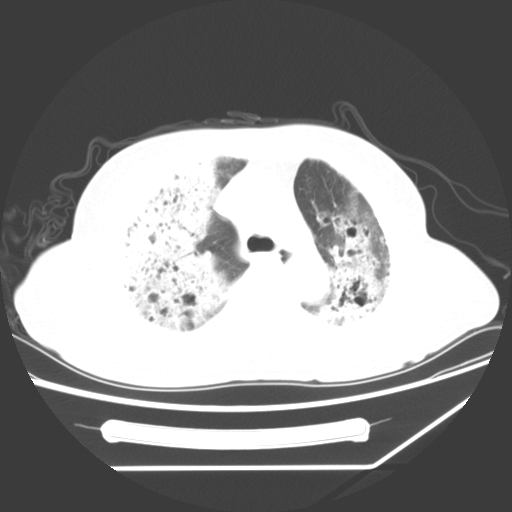

标题: CT25393:病人45岁,咳嗽,吐黄痰带血丝,发热,胸闷月余 [打印本页]

标题: CT25393:病人45岁,咳嗽,吐黄痰带血丝,发热,胸闷月余

1、左肺中央型肺癌并双肺弥漫性转移   2、双肺部感染    3、肺大泡     4、左侧胸腔积液

双侧肺弥漫性病变,可见“空泡征”及“蜂窝征”,考虑肺泡癌可能性大,左侧胸腔积液,考虑胸膜受累可能!

考虑肺泡癌,建议排除感染。

1)不排除肺泡癌可能。2)左侧胸腔积液。